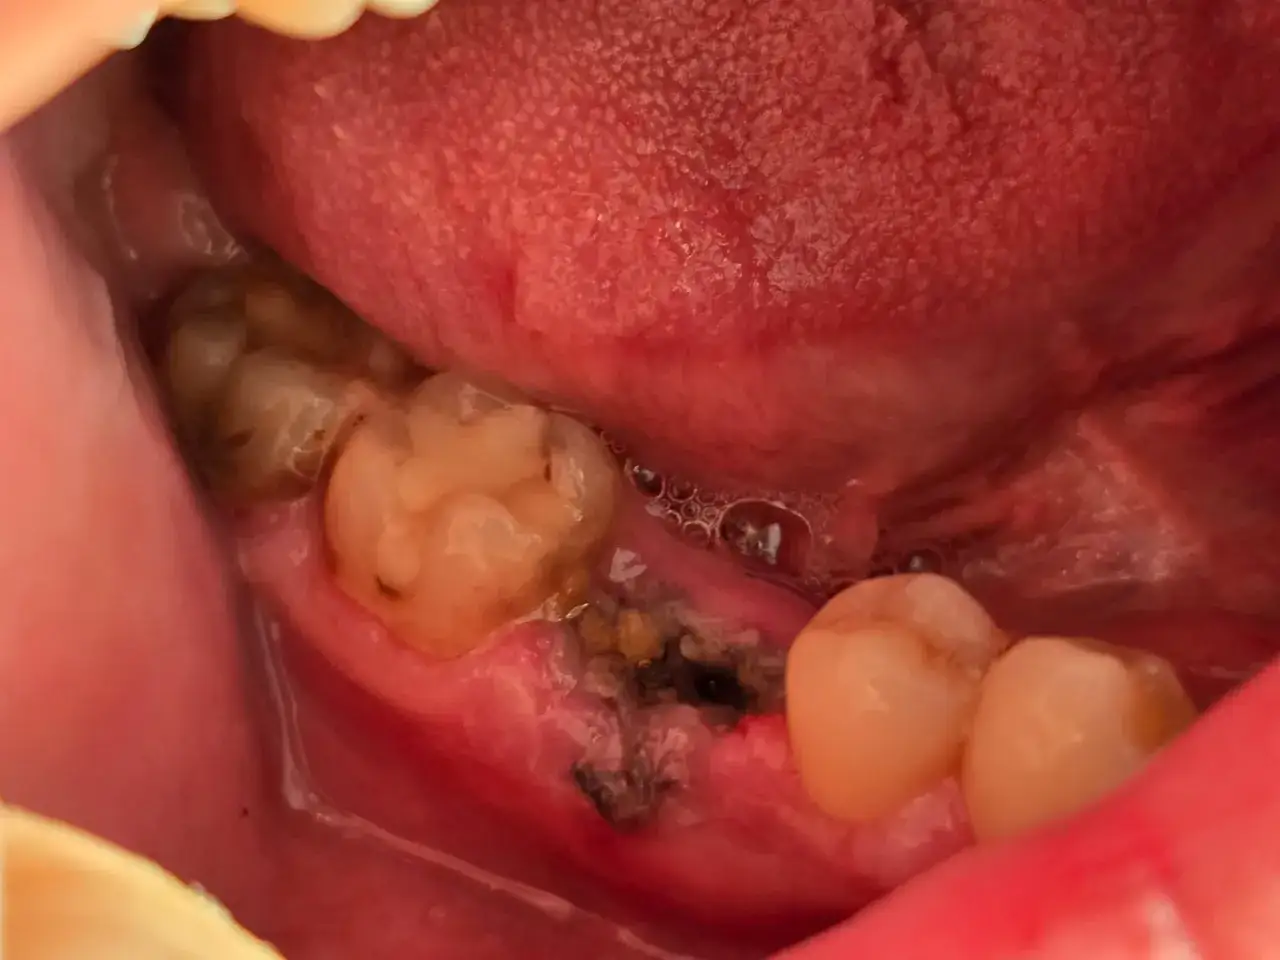

Suchy zębodół: Jak rozpoznać to bolesne powikłanie?

Suchy zębodół, znany również jako puste zębodoły, to jedno z najczęstszych i najbardziej bolesnych powikłań po ekstrakcji zęba. Jego głównym objawem jest silny, pulsujący ból, który zazwyczaj pojawia się 2-4 dni po zabiegu i może promieniować do ucha lub skroni. Często towarzyszy mu nieprzyjemny zapach z ust, a przy zaglądaniu do zębodołu można zauważyć, że brakuje w nim skrzepu, a dno jest "gołe", odsłonięte. Jeśli doświadczasz takich objawów, niezwłocznie skontaktuj się ze swoim dentystą.